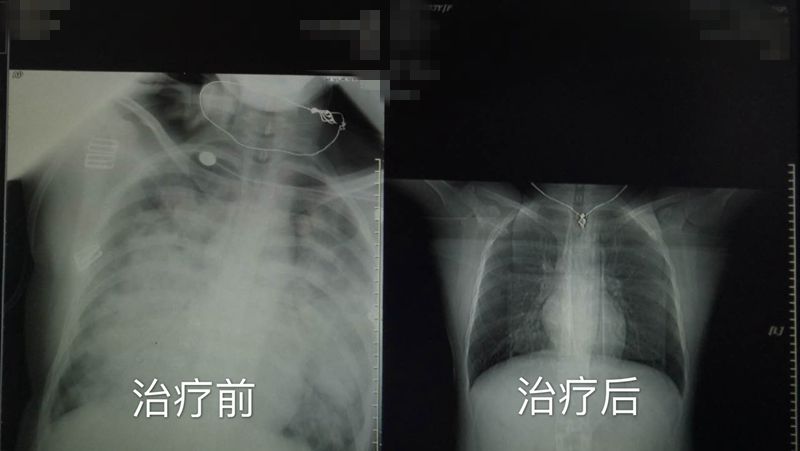

经拍片检查,余女士的两肺渗出(白肺),白肺是肺部严重感染的表现,主要是因为严重的肺部感染导致肺部在胸片上看起来是白花花的一片,且患者血气示低氧,病情重、进展快,随时有生命危险。被确认为“重症肺炎”,转入我院感染科住院治疗。

经呼吸机辅助通气,同时给予药物治疗,经过一周多积极的治疗,余女士两肺渗出性病变较前明显吸收;两侧胸腔少量积液较前吸收,转危为安,并于近日治愈出院。